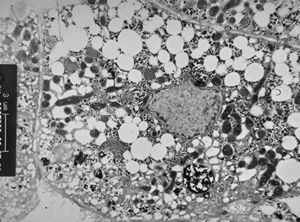

F,1y. | glycogenosis type II.(glycogen dissolved due to UA blockstaining)

F,1y. | glycogenosis type II. (glycogen dissolved due to UA blockstaining)